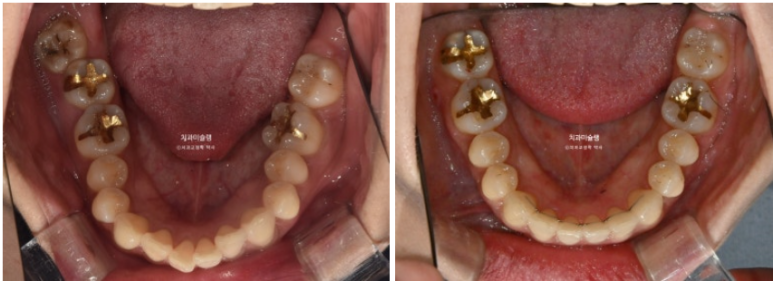

23.08~25.11

교합의 균형이 맞아지면 비로소 좌우 50대 50으로 씹을 수 있게 됩니다.

교정치료가 심미치료라고 오해하는 분들 많으신대요 사실은 기능적으로 이득이 큰 치료입니다.